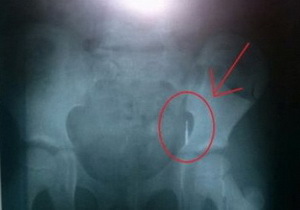

21 января пятилетняя Маша вместе с отцом пришла в поликлинику для пломбирования зуба. Из-за ошибки врача девочка проглотила стоматологическое сверло.

Врач сразу же направила девочку к лору, но тот ничего не обнаружил. Далее маленькую пациентку ждало рентгенологическое обследование. Стоматологическое сверло обнаружили в желудке малышки. Жизни Маши ничего не угрожает, уверяют врачи. Это сверло сделано из медицинского металла, поэтому никакого вреда ребенку не принесет. Врачи уверяют, что в течение 7-10 дней оно должно выйти самовольно. Мать девочки в панике, ведь по ее наблюдениям, сверло до сих пор находится в желудке ребенка. Если сверло не выйдет, то понадобится хирургическое вмешательство, а врач за свою ошибку понесет уголовную ответственность.